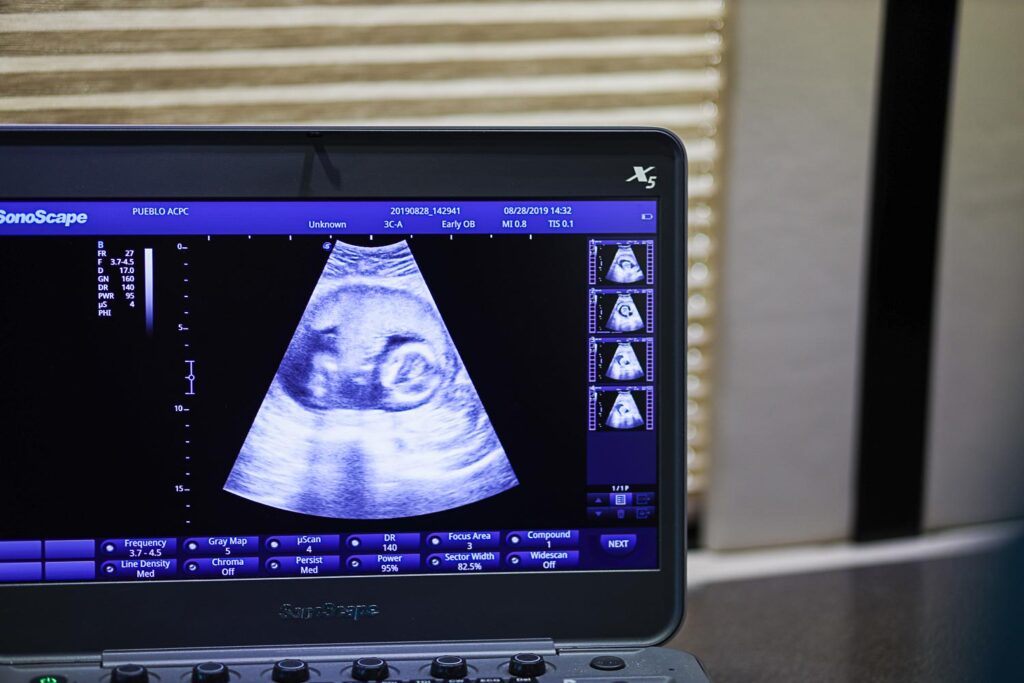

For years, the pro-life cause was portrayed as outdated or purely political—but Gen Z isn’t buying that narrative. Today’s students are the first generation to grow up seeing high-definition ultrasounds on their smartphones and hearing unborn heartbeats through earbuds. They’ve been shaped by science, empathy, and personal experience—not slogans.

Modern technology has made the humanity of the unborn impossible to ignore. A baby’s heartbeat begins at about 21 days after conception, before most women even know they’re pregnant (National Library of Medicine, 2021). By eight weeks, tiny hands and facial features have already formed.

When students see these images, they’re confronted with truth: life begins at conception. That’s not a faith claim. It’s biology.

Each heartbeat heard through an ultrasound isn’t just sound—it’s hope. Hope that one life will be saved, that one mother will feel empowered, and that compassion will outshine controversy.